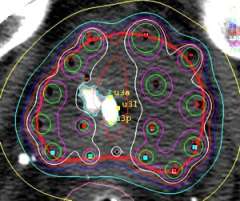

- The physician then uses a template to help direct the treatment tubes called "flexiguides" in and around the prostate. This template has pre-drilled holes arranged in two concentric circles. This circular distribution conforms better to the natural shape of the prostate. The template is held in one hand, while the flexiguides are inserted with the other. Holding the template, rather than having it clamped to the table as in the fixed template technique, allows the physician to tip and angle the template, resulting in more control over where they can place the flexiguides. This is a major advantage as it allows the physician to flare the flexiguides to encompass larger prostates, extracapsular extension, or seminal vesicle involvement.

Below is an example of the standard template that we use for prostate brachytherapy here at UCLA.

Once the flexiguides are in position the template is sutured to the perineum to stabilize the implant.